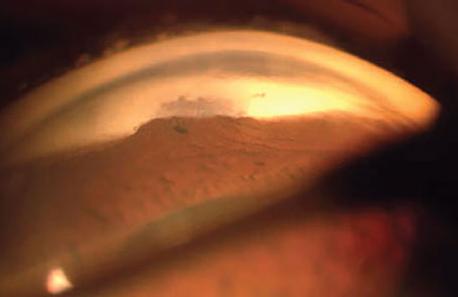

3. 여과포에 큰 파열이 있는 경우.

대부분 여과포가 납작하게 형성되어 있고, 전방도 얕아져있는 경우입니다.

이 경우 수술적인 봉합이 처음부터 필요합니다.

수술후 시간이 지난 경우, 파열이 있는 부분을 바로 봉합하려고 하면, 이미 반흔의 형성으로 인해,

결막이 뻣뻣해져서 당겨지지도 않고, 봉합하다가 찢어지는 경우가 더 많습니다.

따라서 이경우는 주변의 정상적인 결막과 결막하 테논조직을 잡아당겨와서 이를 메꾸어주는 방식으로 치료합니다.

하지만 수술이후에도 여과포 위의 반흔이 심하게 남아 방수여과감소로 이어지게되고,

결국 수술실패가능성이 커집니다.